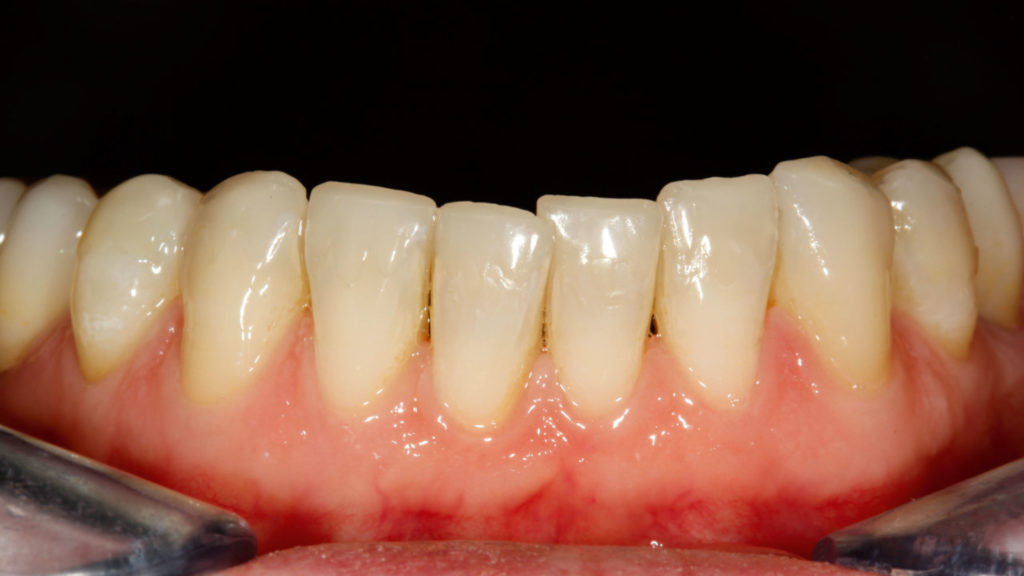

Bei der Patientin wurde über eine funktionelle Initialtherapie die neue vertikale Bisshöhe mittels Schiene über einen Zeitraum von sechs Monaten etabliert (Abb. 4). Für den Aufbau der Zähne zum dauerhaften Stabilisieren der VDO waren keramische Restaurationen geplant. Im ersten prothetischen Therapieschritt sollten die Zähne im Oberkiefer versorgt werden. Dafür wurden alle Zähne präpariert, wobei ein substanzschonendes Vorgehen im Fokus stand. Im Seitenzahngebiet sollten eine Brücke (25 auf 27) und ansonsten Einzelkronen gefertigt werden. Die Oberkiefer-Frontzähne wurden für die Aufnahme von 360°-Veneers präpariert, da aufgrund der Bisshebung auch die palatinalen Bereiche in die Restauration eingebunden werden mussten. Um die validierte Bisshöhe zu stabilisieren, erhielt die Patientin nach der Präparation im Oberkiefer beziehungsweise dem Einsetzen der provisorischen Versorgung die Schiene im Unterkiefer wieder eingegliedert. Im Labor wurden vollkeramische Restaurationen aus Lithiumdisilikat angefertigt und zugleich die noch nicht präparierten Zähne im Unterkiefer additiv aufgebaut. Es wurde eine Art „Deckel“ aus Komposit in entsprechender Morphologie und Bisshöhe angefertigt. Unmittelbar nach der adhäsiven Eingliederung der keramischen Restaurationen im Oberkiefer konnten diese temporären Versorgungen ohne Präparation auf den unteren Zähnen befestigt werden. Die Patientin erhielt so die Möglichkeit, die Situation – die neue VDO – nochmals zu testen, nun bereits mit neu versorgtem Oberkiefer. Im zweiten prothetischen Therapieschritt wurden die Zähne im Unterkiefer präpariert. Im Frontzahnbereich (Zähne 34 bis 44) kam der Pfullinger Wellenschliff zur Anwendung (Abb. 5). Die Vorteile dieser Präparationsart in diesem Fall waren die geringe Invasivität, das vereinfachte Handling bei der Herstellung der Frontzahnveneers sowie deren Eingliederung. Aufgrund des reduzierten Präparationsdesigns musste nur in den vestibulären Bereichen Substanz abgetragen werden. Der Wellenschliff erfordert Fingerspitzengefühl und Präzision – ein geringer zeitlicher Mehraufwand, der sich jedoch aufgrund der Vorteile, die diese Präparationsart mit sich bringt, lohnt. Im Seitenzahnbereich wurden die Zähne für die Aufnahme einer Brücke von Zahn 45 auf Zahn 47 sowie für Kronen und Teilkronen von 35 bis 37 vorbereitet. Nach einer Überabformung (Abb. 6) wurde die Grundzahnfarbe als Basis für die Rohlingauswahl bestimmt (Abb. 7).

Im Labor konnten die vollkeramischen Restaurationen in der Presstechnik hergestellt werden (Abb. 8 bis 11). Die exakte Bisshöhe wurde zuvor im Mund evaluiert. Herstellung und Eingliederung der Veneers gestalteten sich dank des Wellenschliffs deutlich einfacher als mit anderen Veneer-Präparationsarten, da die Restaurationen am Zahn eine definierte Position hatten. Die adhäsive Eingliederung folgte den bekannten Abläufen. Die keramischen Restaurationen wurden geätzt beziehungsweise für das Verkleben konditioniert (Abb. 12). Nach dem Reinigen der Zähne wurden die Oberflächen mit Phosphorsäuregel vorbereitet, abgespült und getrocknet, mit Primer vorbehandelt, und es wurde Haftvermittler beziehungsweise Bonder aufgetragen (Abb. 13 bis 17). Nach dem Applizieren des Befestigungsmaterials konnten die Restaurationen eingegliedert und Materialüberschüsse entfernt werden (Abb. 18 und 19). Nach der Lichthärtung wurden die Ränder geglättet und die approximalen Kontakte angepasst sowie final poliert (Abb. 20 bis 24). Dabei zeigte sich ein weiterer Vorteil des Pfullinger Wellenschliffs. Der Übergang zwischen Zahn und Keramik ist dank des „diffusen“, bewusst unregelmäßig angelegten Präparationsdesigns optisch kaum wahrzunehmen. Eine Kontrolle der funktionellen Gegebenheiten bildete den Abschluss der prothetischen Therapie. Die in der Initialphase stabilisierte neue vertikale Bisshöhe konnte 1:1 mit den keramischen Restaurationen übernommen werden (Abb. 25).